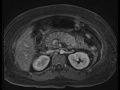

Acute Pancreatitis

Multiple MR images demonstrate a diffusely enlarged, edematous pancreas with surrounding fluid and fat stranding, particularly evident on the fat-suppressed images, compatible with acute pancreatitis